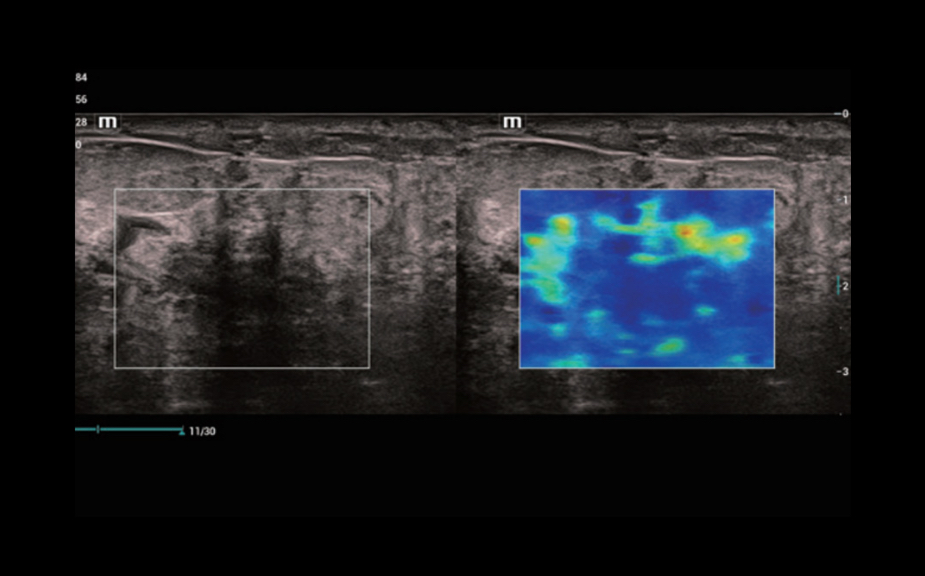

Diagnostyka zmian ogniskowych za pomoc? obrazowania ze ?rodkiem kontrastowym UWN+

Wykorzystanie zar├│wno sygna?├│w drugiej harmonicznej oraz nieliniowych sygna?├│w podstawowych

Wi?ksza czu?o?? w przypadku s?abszych sygna?├│w i d?u?szy czas dzia?ania ?rodka przy ni?szym MI

CEUS - nowotw├│r w?troby z przerzutami

CEUS - perfuzja w gruczolaku tarczycy